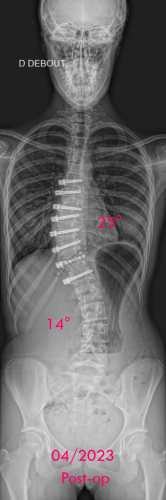

Images de scolioses opérées 16 janvier 202418 janvier 2023 par Damien Scoliose idiopathique - VBT -1 Chirurgie de modulation de croissance (VBT) Scoliose idiopathique - VBT -1 - pré-op Scoliose idiopathique - VBT -1 - pré-op en traction Cliché réalisé pour tester la réductibilité de la scoliose Scoliose idiopathique - VBT -1 - post-op immédiat Scoliose idiopathique - VBT -1 - 3 mois post-op Scoliose idiopathique - VBT -1 - 10 mois post-op